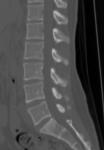

脊椎CT検査

椎体の変形や骨折、配列の乱れ、腫瘍などを任意の断面で観察することができます。

画像処理によって、立体的に表示させることも可能です。